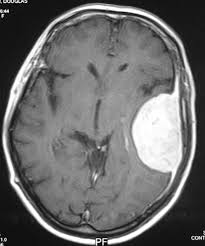

අපි මෙහෙම හිතමු , මොළය ඇතුළෙ අළුත් ගෙඩියක් හැදෙනවා ..ටිකෙන් ටික ලොකු වෙනවා ..දැන් මොකද වෙන්නේ , මොළයේ සාමාන්‍ය කොටස් තෙරපෙනවා ..ඒ විදියට තෙරපුනාට මොළයට පුළුවන්ද හිස් කබලත් කඩාගෙන ලොකු වෙන්න ..බැහැ ..ඒ නිසා දැන් මොකද වෙන්නේ , අර ගෙඩිය නිසා අඩුවන ඉඩකඩ ඇතුලේ , සහ හිස් කබල  කියල හුණු ගල් ආවරණය ඇතුලේ මොළය තද පීඩනයකට පත්වෙනවා ..ඒ එක්කම පැල් පොල් මදයක් වගේ තියෙන මොළ ගෙඩිය මිරිකුණාම , ඒ එක්ක තියෙන C.S.F වලත් පීඩනව වැඩිවෙනවා ...ඔන්න ඔය සිදුවීම තමයි අපේ මේ කතාවේ සිද්ධාන්තය ..මේ විදියට පීඩනය වැඩි වන්නට ගෙඩි (Tumors ) මේව පිළිකාමය හෝ නොවන අවස්ථාවේ කුමක් වුවත් “ගෙඩියක් ආවොත් “ මොළය ආශ්‍රිත පීඩනය ඉහළ යනවා..ඒ විතරක් නොවෙයි , හිස් කබල ඇතුළේ කොතනක හරි ඉදිමීමක් වුනොත් ...ඒ කියන්නේ Meninigitis (Meninge+itis මෙනින්ජි ප්‍රදාහය) හෝ Encephalitis (මොළයේ මිදුළුමය encephalo +itis කොටස් වල ප්‍රදාහය - දැන් මතකද මන්දා අපි මේ itis ගැන අර ගල් ගුහාවේ මාරයා ලිපියෙදි කතා කළා) වැනි මොළය තුල ප්‍රදාහික තත්ත්වයක් ආවත් මේ විදියටම I.C.P. වැඩි වෙනවා (I.C.P.-Intra cranial pressure) තවත් හේතු ....ඔව් යම් විදියකින් මොළය ඇතුලට ලේ වැගිරීමක් වෙනවා නම් ...(Intracranial hemorrhage ) කොහොමද වෙන්න පුළුවන් , ..? මොළය ඇතුලේ තියෙන ලේ නහර විය පත් වීම , නහර වල ඇති වන යම් දුර්වලතා ...නහර පිම්බීම් (Aneurysm ) තිබීම් වගේ අවස්ථා වලදීත් .සමහර විට පාළනය නොකළ අධිරුධිර පීඩනයේදීත් මේ විදියට මොළය ඇතුලට ලේ ගලන්නට පුළුවන් , අනික ඉතින් රිය අනතුරක් හරි ඔළුවට දරුණූ පහරක් හරි වැදුනම මේක වෙන්න පුළුවන් බව ආයෙ ඉතින් කියන්න ඕනයැ නේද ...? මීට අමතරව මොළය ඇතුලේ තියෙන C.S.F තරළය හරි හැටි ගලා නොයාම හෝ වැඩිපුර ස්‍රාවය විම නිසාත් මේ වගේම පීඩනය වැඩිවන්නට පුළුවන් ..ඒත් බොහෝ අවස්ථාවල මේ තත්තවය උපතින්ම එන අවස්ථා වැඩි නිසා ප්‍රතිකාරයටන්ට යොමුවීමේ ඉඩ වැඩියි ..නමුත් ලොකු වුනාම එන I.C.P.වැඩිවීමට ප්‍රතිකරයන්ට යොමු වෙන්නේ හුඟක් වෙලාවට ප්‍රමාද වෙලා ...

ඉතින් මේ මුල් ලක්ෂණ කිහිපයක් පිළිබඳ දැනගන්නට ලැබුණොත් , කළ යුතු හොඳම දේ කිට්ටුවම තියෙන රජයේ රෝහලට යන  එක , (ඔබේ පවුලේ වෛද්‍යවරයා මගින් වුවත් කමක් නැහැ ) ..එහිදි මුලික පරීක්ෂණ කිහිපයකින් පස්සේ “මොළයට යම් අනතුරක් “ යැයි සැක කළොත් M.R.I. හෝ C.T. scan වැනි පරික්ෂණත් , කරන්න ඉඩ තිබෙනවා . තත්ත්වය එසේ නම් ඖෂධ මගින් පාලනය කළ නොහැකි නම් බොහෝ දුරට , දැඩි සත්කාර පහසුකම් , සහ ස්නායු ශල්‍ය දැඩි සත්කාර පහසුකම් සහිත රෝහලක පහසුකම් ලබා දෙන්නට කටයුතු කරාවි , මොකද මෙහිදි මොළය තුල පීඩනය අඩු කරන්නට වගේම ජීවිතය පවත්වා ගන්නටත් මේ දැඩි සත්කාර ඒකක වල පවතින තාක්ෂණික උපකරණ අත්‍යවශ්‍යයි ...ඒ එක්කම මීට හේතුව මුලින් කීව වගේ මෙනින්ජයිටිස් හෝ එවැනි ප්‍රදාහයක් හෝ ආසාදනයක් නම් ඊට අවශ්‍ය ඖෂධිය ප්‍රතිකාරත් ආරම්භ කරාවි ..